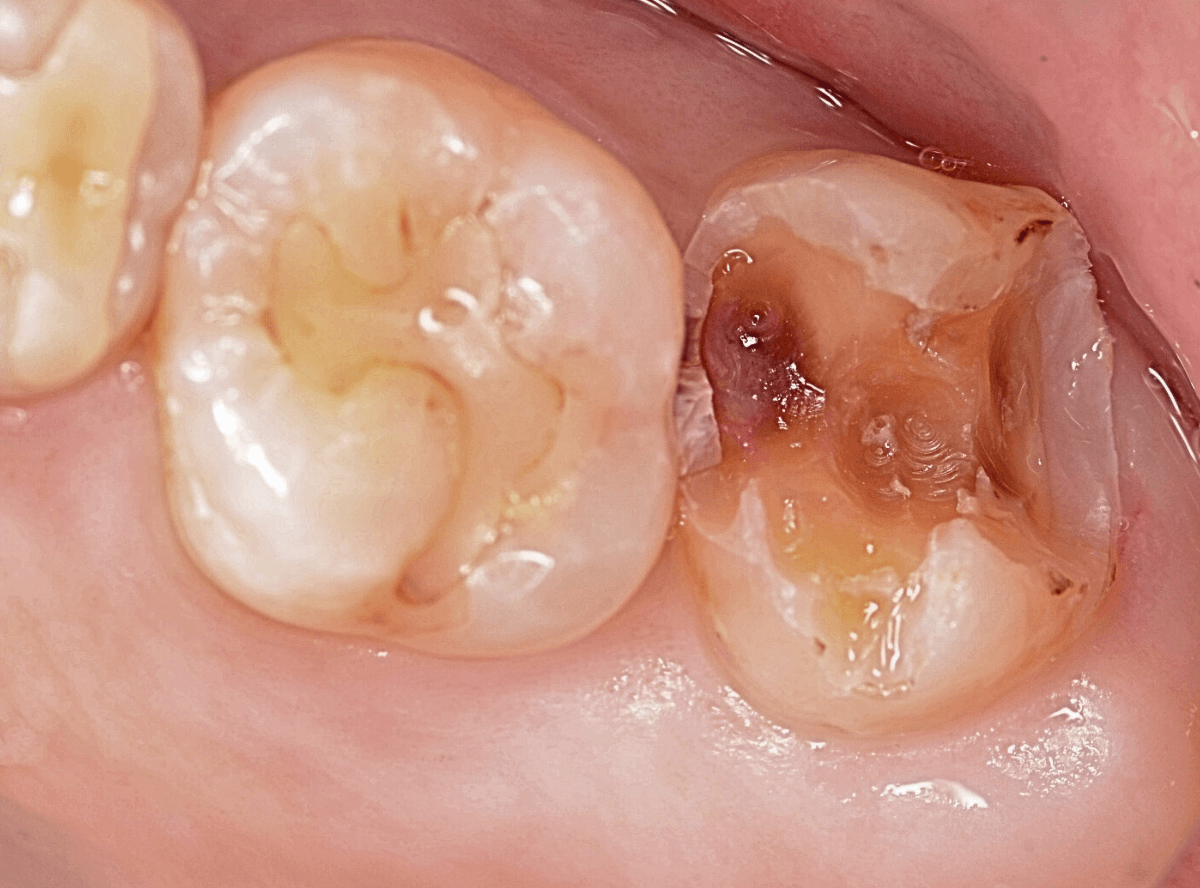

Case.4 金属の側面から深く進行した虫歯

上の奥歯が、しみたり痛む時があるという患者さんが来院されました。

お口の中を拝見した瞬間「これは重症そうだ(><)」と思いました。

さて、虫歯はどこでしょうか。

一番奥の歯のつめものわきに穴が開いています。

こういった部分の虫歯は中で大きな虫歯になっている事が多いです。

加えて「しみる、痛い」という症状があるのですから、なおさらです。

レントゲン写真で確認すると。

想像通り、大きな虫歯でした。

手前の歯も、虫歯がありそうな感じです。

ほぼ歯の神経(青色)まで達している虫歯(赤色)です、今回は、歯の神経を残すのは難しいかもしれません。

麻酔をして、金属を外しました。

赤く染まったところが虫歯です。

真っ赤に染まっていることから、まだまだ虫歯が深そうなのが想像つきます。

今回も、慎重に虫歯を除去しました。

何とか、神経の薄皮一枚ギリギリのところで食い止められましたが・・・、いつものように神経を保護するお薬をつめて、痛みが出ない事を祈ります。。。

しばらく経過観察後、無事につめ物を作り直すことができました。

金属のつめ物は、熱を通しやすいので、つめ物を入れた後に冷たいものがしみるなどの症状が出る事がありますので、さらに経過観察が必要ですが、今のところ症状もないそうです。